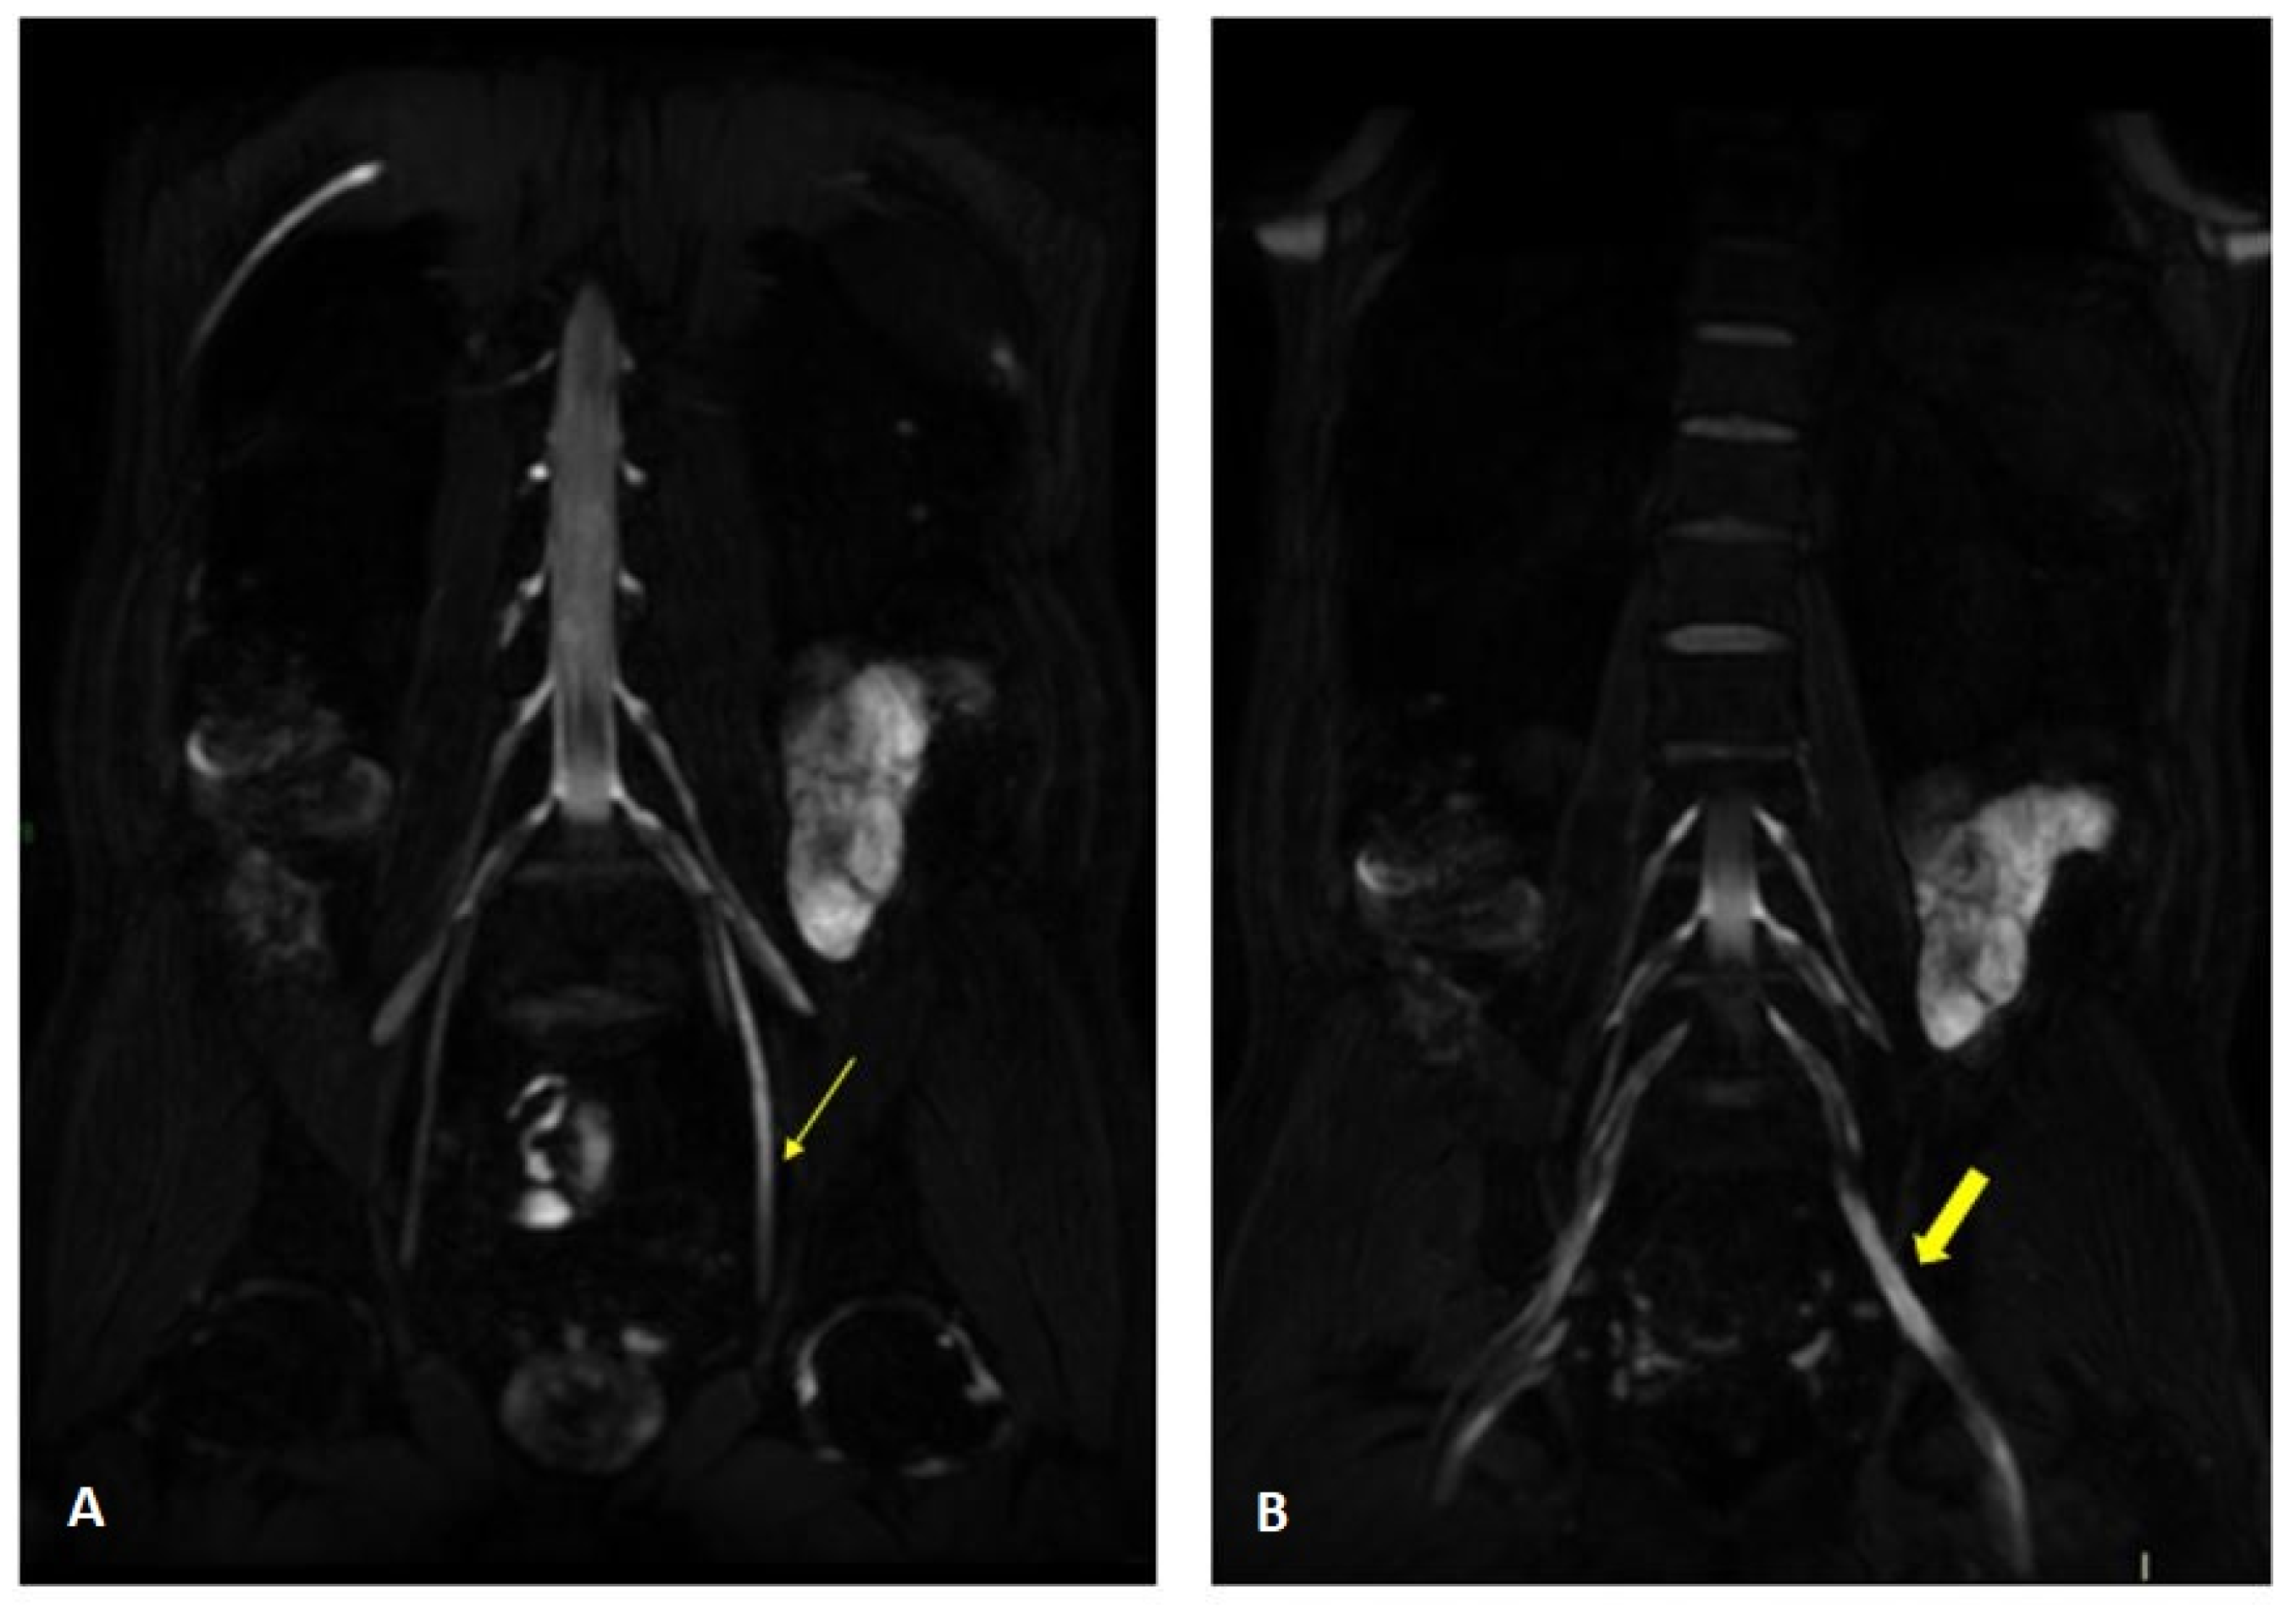

Figure 4.

MR 3D cube nerve images show thickening and T2 hyperintensity of the left obturator nerve (thin arrow in A) and lumbosacral trunk (thick arrow in B) compared to the contralateral one (transverse diameter on left L5 root 7.7 mm (n.v. * 5.99 ± 0.66) and on left S1 root 9.1 mm (n.v. * 5.27 ± 0.53). * Normal values (n.v.) according to the recent study of Su X et al. [20].

Figure 6.

MIP (Maximum Intensity Projection) reconstructions of the 3D cube nerve MR sequence of the lumbosacral plexus show regular size and signal intensity of lumbar and sacral roots.